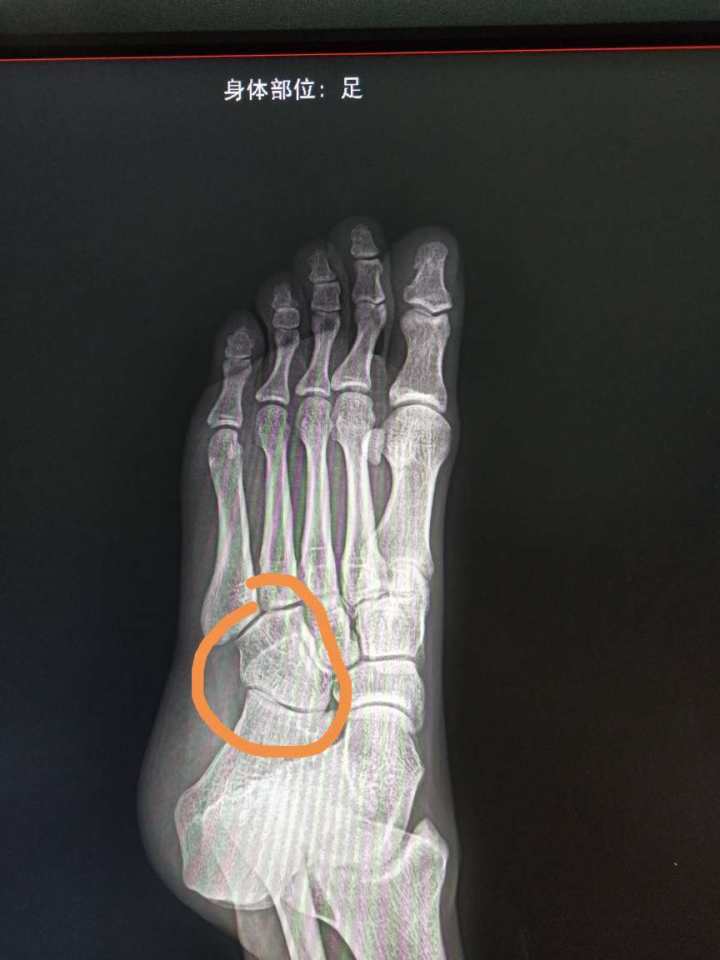

轻微骨裂拍的x片 看不懂 请问已经好了吗?

有没有骨科医生帮我看下到底骨裂位置在哪?说是内踝骨骨裂,一直没看